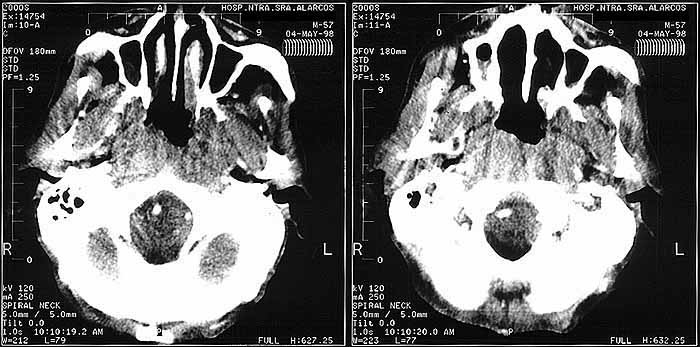

fig. 11

Figura 11. TAC Cavum.